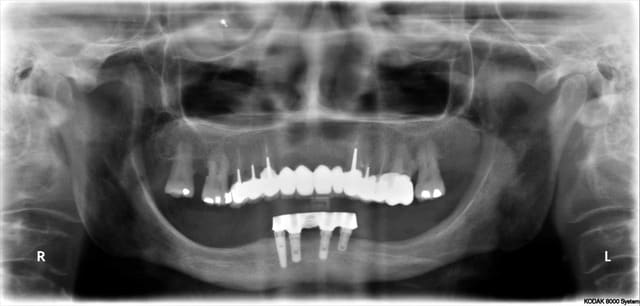

pano 5 et photo 6 ce matin